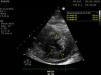

A 41-year-old woman with humoral deficiency and monoclonal gammopathy IgG lambda presented to the ER with fever and weakness and was diagnosed with an influenza A-related respiratory infection. Twenty-four hours later, she was admitted to the intensive care unit because of severe hypotension, requiring norepinephrine up to 0.5 μg/kg/min, hypoalbuminemia, and hemoconcentration. She was diagnosed with systemic capillary leak syndrome (SCLS) with intramyocardial edema (IME). SCLS is a condition characterized by the leakage of plasma and proteins into the interstitial compartment. It is associated with monoclonal gammopathy, and often occurs after an upper respiratory tract infection, with IME being a rare complication in this disease. In our patient, the transthoracic echocardiogram (TTE) performed at admission revealed that left ventricle ejection fraction (LVEF) was at the lower normal limit (LVEF 50%-55%) with restrictive physiology and evidence of diffuse myocardial thickening, as shown in the TTE images: parasternal long-axis view (Fig. 1 and Video A), parasternal short-axis view at apical level (Fig. 2), and apical four-chamber view (Fig. 3). This thickering was likely due to IME, since a TTE performed 1 month earlier showed normal myocardial thickness (Fig. 4, parasternal long-axis view). Treatment with immunoglobulins and corticosteroids was prescribed, but unfortunately, the patient died 24 hours after admission due to refractory shock.